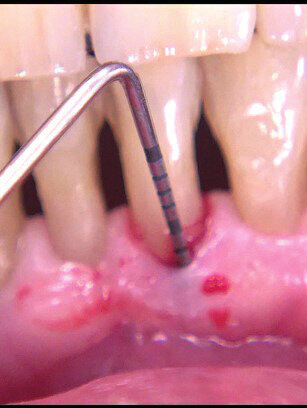

Il paziente di anni 33 viene inviato per trattamento di un gonfiore gengivale apparso circa 1 mese prima. È stato trattato con scaling e root planing senza ottenere il risultato voluto. All’esame obiettivo presenta una lieve gengivite interprossimale con infiammazione e gonfiore limitato alla parte vestibolare di 2.1 con sondaggio di 5 mm vestibolare e 7 mm disto-vestibolare (Fig. 1). La superficie della radice era stata strumentata una settimana prima e si presenta senza residui di tartaro e senza riassorbimenti esterni. Viene scelta l’applicazione di Ozosan Gel per ridurre subito i sintomi che limitavano la capacità del paziente di applicare una corretta igiene orale e per la sua azione antibatterica ma anche stimolante la guarigione. Ozosan Gel viene applicato per 8 minuti - azione anti batterica - seguito da lavaggio con fisiologica. Da subito il paziente segnala riduzione del dolore e viene istruito a uno spazzolamento delicato a roll con spazzolino morbido. Viene rivisto dopo 2 giorni ed effettuata una nuova applicazione di ozono. Controllo a 5 gg (Fig. 2), e applicazione di Ozosan Gel per due minuti per stimolare la guarigione (Fig. 3). Controllo a 2 sett. (Fig. 4) dove si nota recessione dei tessuti che erano stati strumentati in modo aggressivo. Guarigione a due mesi dove i tessuti stanno ricoprendo la recessione (Fig. 5).

Fig. 2 - Guarigione a 5 gg. Tessuti ancora edemetosi. Viene fatta una terza applicazione di ozosan per 2 minuti.

Fig. 3 - Applicazione di Ozosan per 2 min.